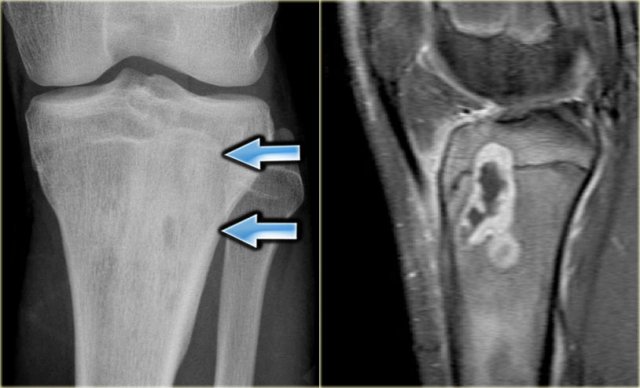

Here two patients with quite similsr findings on the radiographs.

Both have small osteolytic areas surrounded by sclerosis.